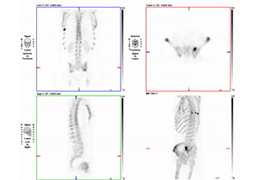

Multi-planar slicing.

Oblique slicing.

Side-by-side comparative assessment for pre- and post-operative scans.